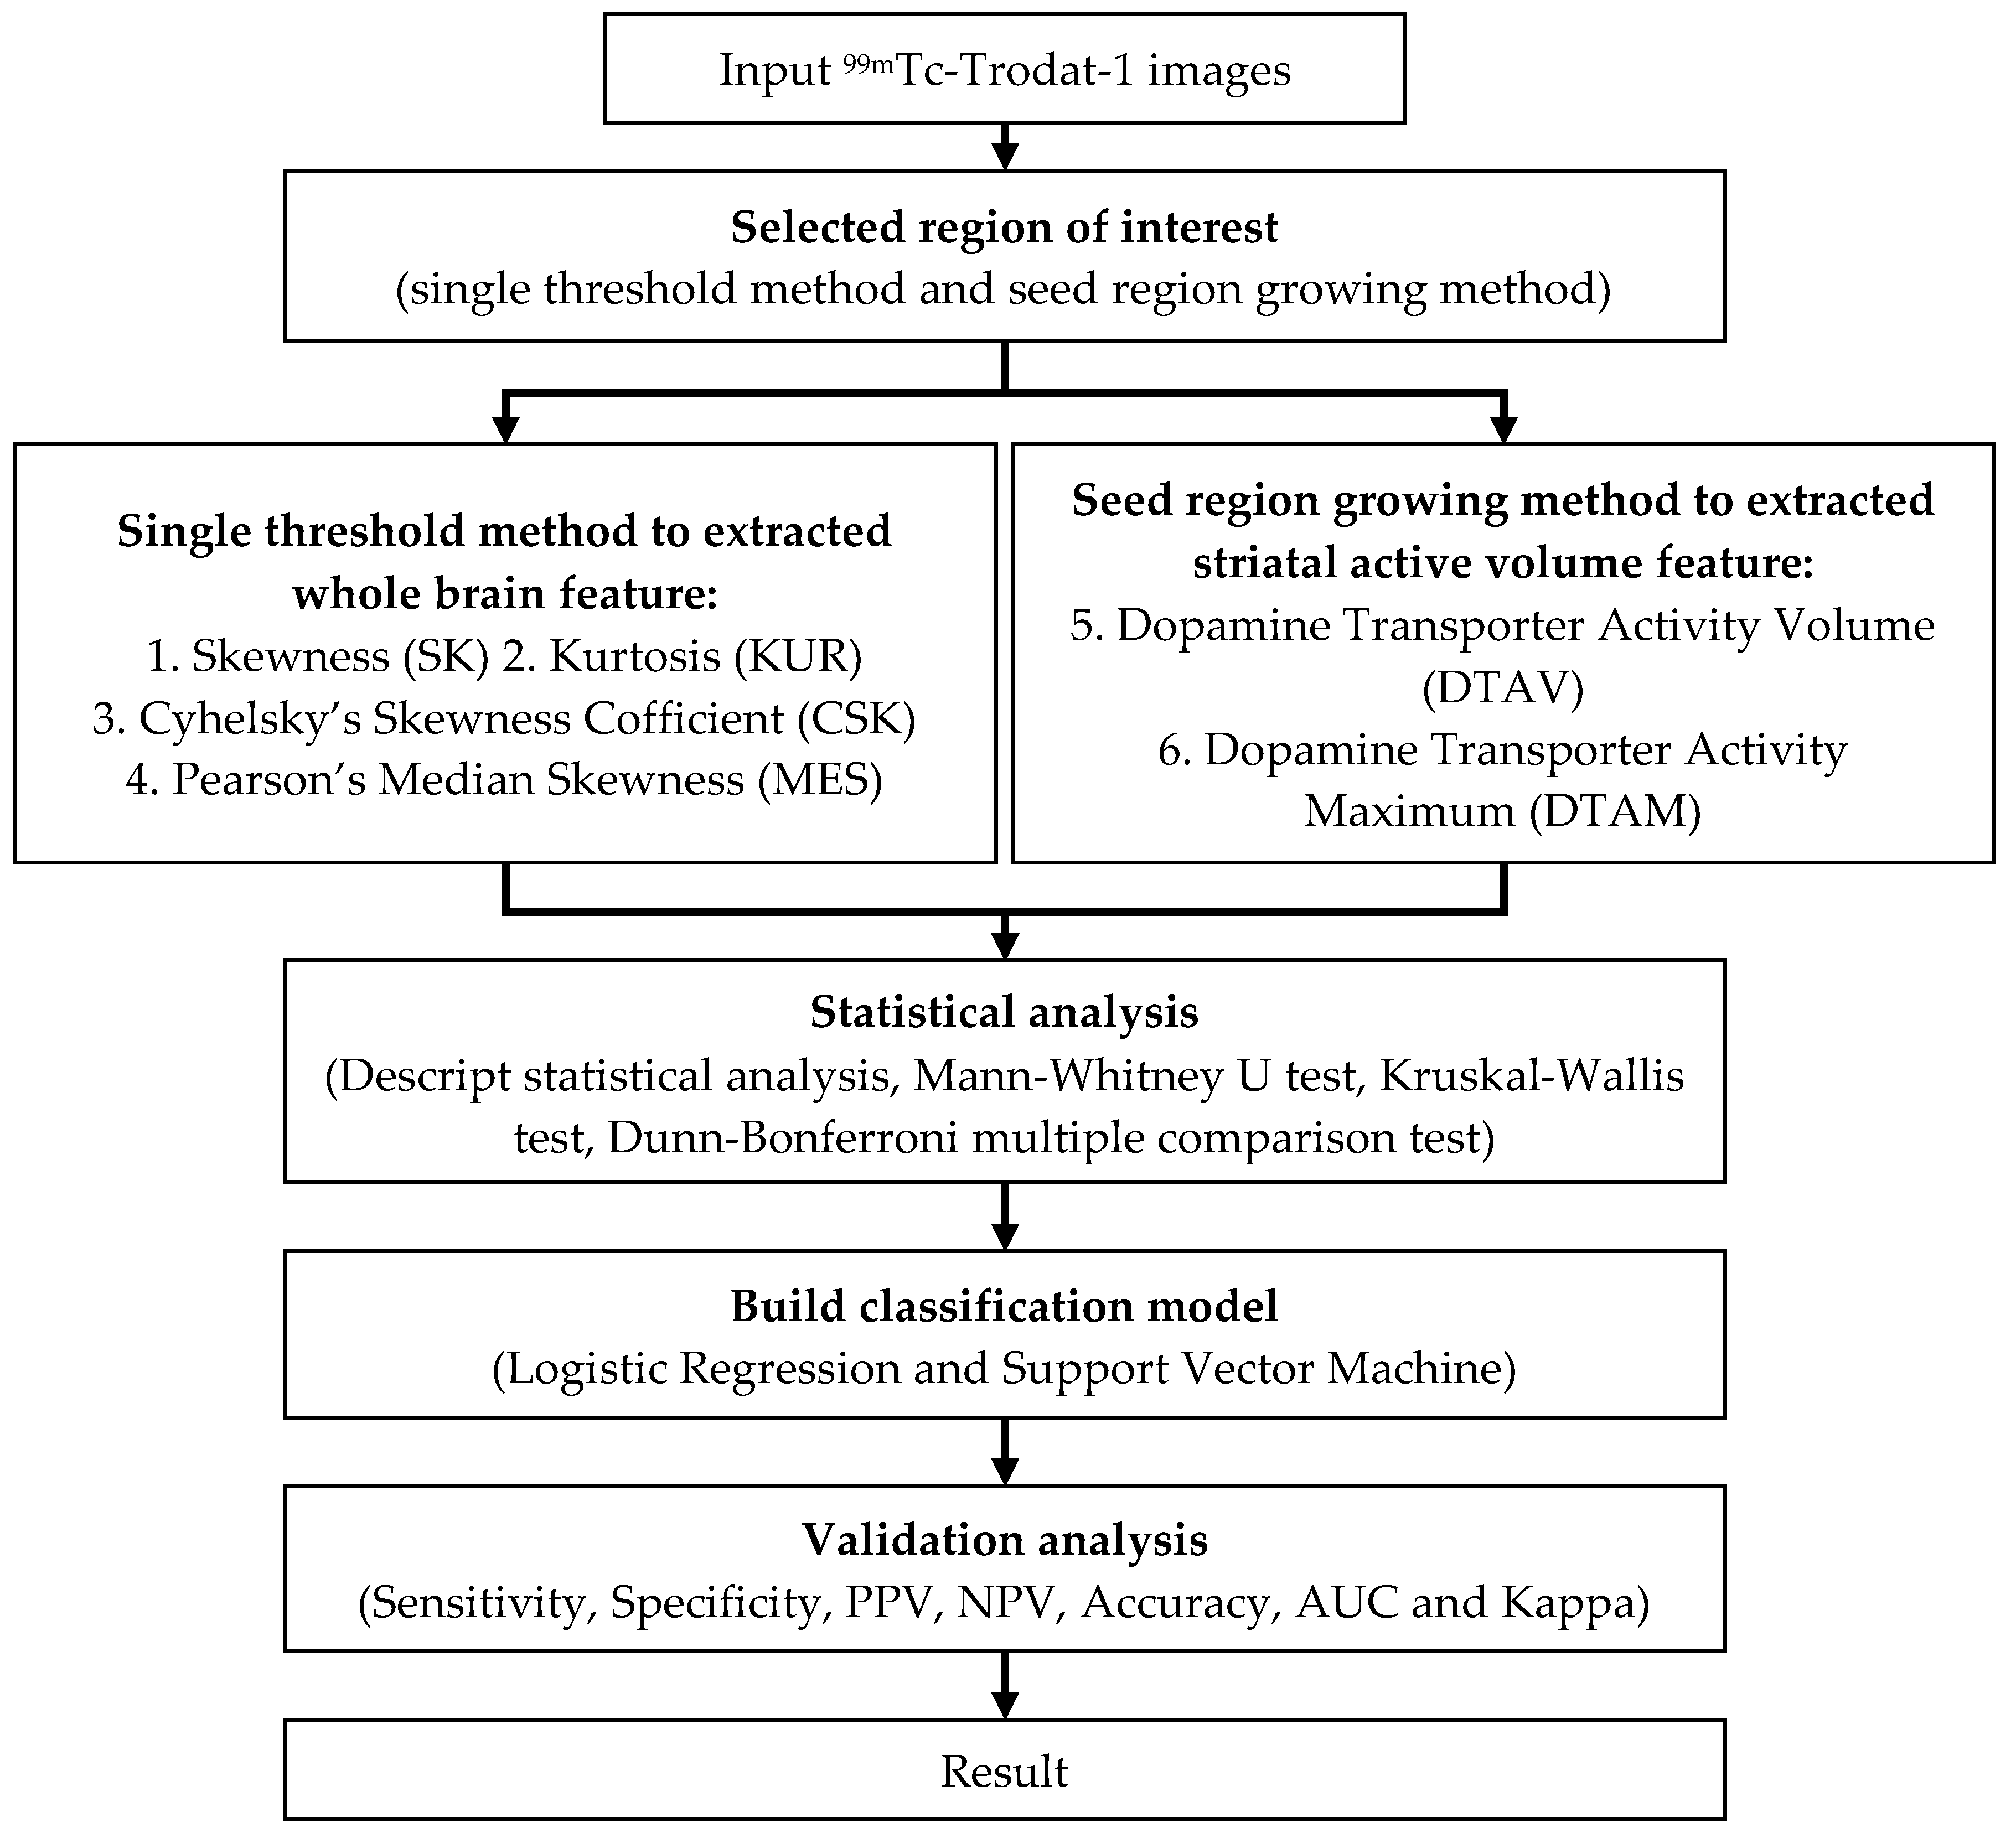

2.3. Experimental Design

2.4. Classification Implementation